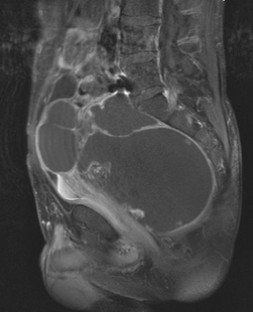

Große Raumforderungen im kleinen Becken können die Harnblase verdrängen und Blasenfunktionsstörungen mit unterschiedlicher Symptomatik hervorrufen. Wir beschreiben den Fall eines 42-jährigen Patienten, der über eine Harnstrahlabschwächung und Restharngefühl bei reduziertem Blasenfüllungsgefühl seit frühester Jugend berichtete und nach zahlreichen konservativen Therapieversuchen neurourologisch evaluiert werden sollte. Bei der Diagnostik zeigte sich eine große zystische, die Blase verdrängende Raumforderung, die einer Retentionsmukozele (bei Zustand nach konnataler Analatresie und chirurgischer Versorgung) entsprach und operativ entfernt wurde.

Large pelvic masses can displace the urinary bladder and cause bladder dysfunction with various symptoms. We report the case of a 42-year-old man who described a feeling of reduced urinary stream and bladder filling and residual urine since his youth. After various unsuccessful conservative treatments, the patient was evaluated by our neurourologic department. The diagnostic workup revealed a large cystic mass that displaced the urinary bladder. Histopathological examination showed a retention mucocele (the patient had been surgically treated for connatal anal atresia). The lesion was surgically excised.

Abb. 2